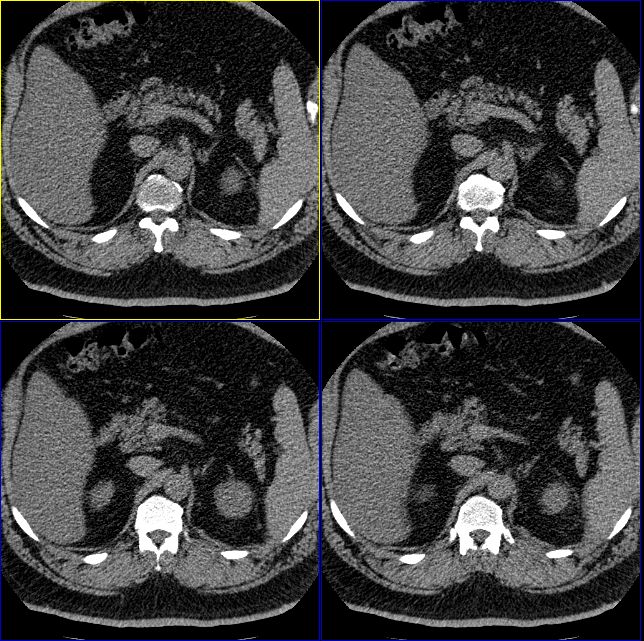

男性,37岁。体型极度肥胖,达300余斤。

标题: 双侧肾上腺没有问题么?

怎么回事啊,难道肾上腺没有问题么?右侧肾上腺有明显的脂肪性类圆形肿物,左侧也觉得有增生性改变。我们诊断为右肾上腺髓样脂肪瘤,左侧肾上腺增生。大家再仔细看看。

右侧肾上腺好像有一个类圆形的囊性包块,内部密度象是脂肪

1.肾上腺区囊性占位

2.脂肪肝

只能考虑有脂肪肝,至于右侧肾上腺“病变”会不会就是内外支间的脂肪组织?